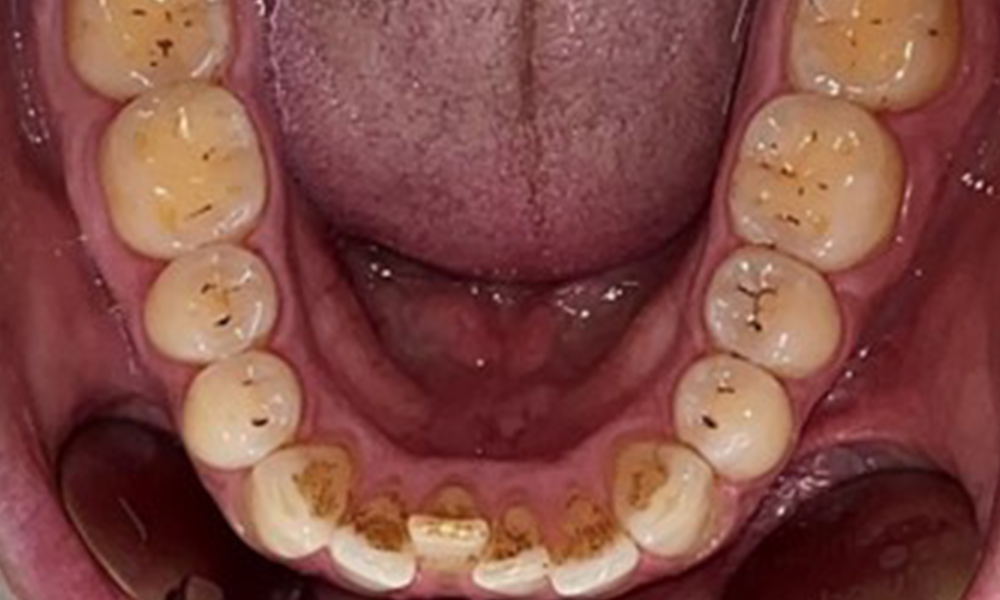

Dentaler Befund

Dental zeigt sich ein vollbezahntes Gebiss mit 28 Zähnen. Auffällig sind Erosionen und Attritionen

(Abb. 4, Abb. 5). Der Patient trägt seit vielen Jahren nachts eine Schiene mit adjustiertem Aufbiss aufgrund Bruxismus. Die Erosionen sind auf den langjährigen Konsum isotonischer Getränke zurückzuführen. Parodontaler Knochenverlust und aktive kariöse Läsionen sind nicht vorhanden.